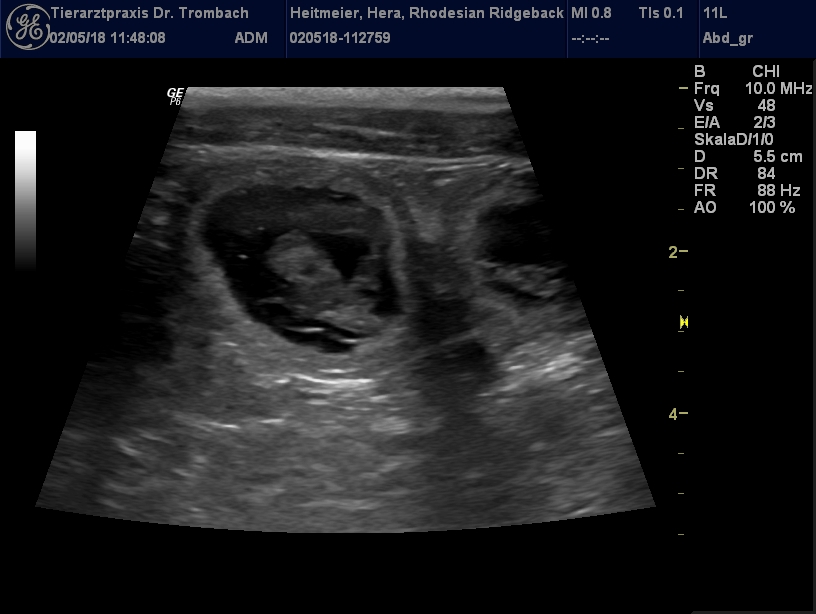

Der Ultraschall vom 02.05.2018 brachte freudige Gewissheit